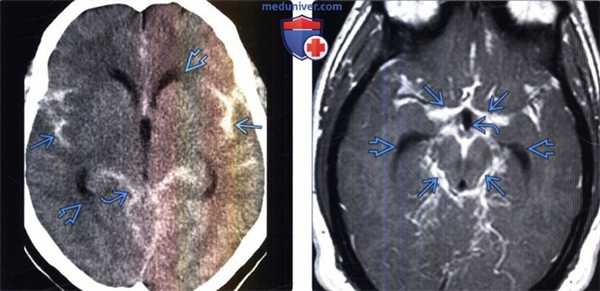

(Слева) Бесконтрастная КТ, аксиальный срез: в базальных цистернах, а также в сильвиевых бороздах определяется острое субарахноидальное кровоизлияние. Кроме того, отмечается внежелудочковая обструктивная гидроцефалия на ранней стадии ее развития с легким снижением плотности мозговой ткани в перивентрикулярных отделах вследствие интерстициального отека.

(Справа) МРТ, постконтрастное Т1-ВИ, аксиальный срез: определяется протяженное контрастирование лептоменинкс в базальных цистернах при нейросаркоидозе. Обратите внимание сообщающуюся гидроцефалию на ранней стадии ее развития с расширением III желудочка и височных рогов боковых желудочков.